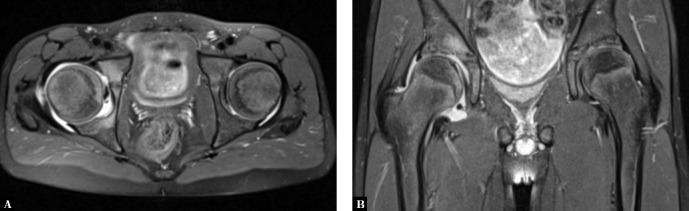

根据国际风湿病联盟协会的分类,青少年脊柱关节炎可能至少存在于青少年特发性关节炎的3种亚型中。与成人脊柱关节炎不同,大多数儿童的青少年脊柱关节炎始于外周关节和附着点的炎症,而骶髂关节炎和脊柱炎可能在疾病发作多年后才会出现。外周关节受累使得青少年脊柱关节炎难以与其他青少年特发性关节炎亚型相区分。骶髂关节炎,尤其是脊柱炎,虽然在儿童期并不常见,但可能表现为腰痛。在临床实践中,即使磁共振成像能更准确地诊断骶髂关节炎,大多数情况下仍会对骶髂关节或骨盆进行X线检查。青少年脊柱关节炎患者的疾病分类标准和影像学检查建议均未考虑到这一优势。对临床怀疑有骶髂关节炎的儿童和青少年使用磁共振成像进行评估将有助于早期诊断、识别炎症变化及进行治疗。在本文中,我们展示了青少年强直性脊柱炎、青少年银屑病关节炎、反应性关节炎伴脊柱关节炎以及与炎症性肠病相关的青少年关节病中青少年脊柱关节炎的影像学特征。